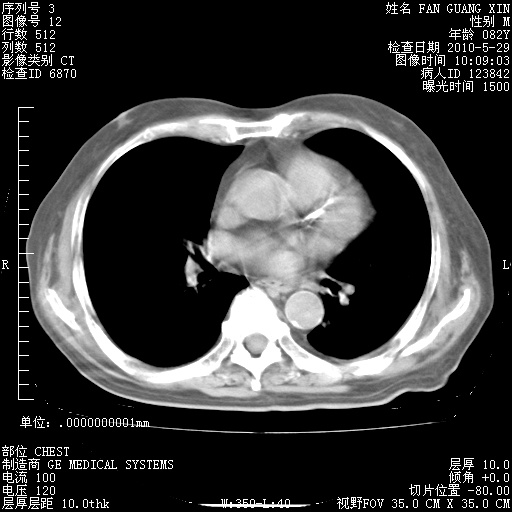

再治疗10天后的肺部CT 纵膈窗